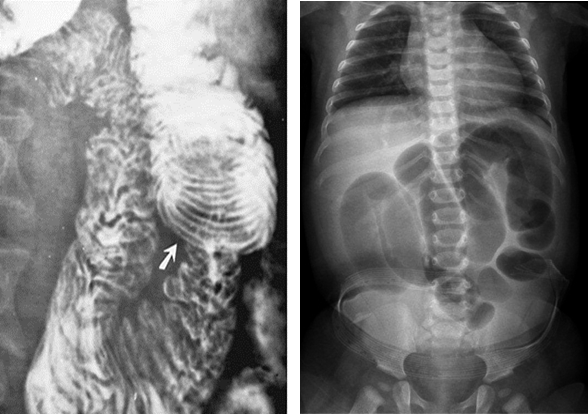

Crohn’s Disease

is an idiopathic, chronic, inflammatory bowel disease (IBD).

Although it can affect any part of the GI tract, the most affected part is the terminal area of the ileum.

It is most common in young adults.

Cause is unknown

It causes long term inflammation of the bowel.

Radiological Appearance:

Skip lesions, in severe cases it resembles a cobblestone appearance

Ulcerative Colitis

is an idiopathic inflammatory disease of the bowel.

Begins in recto-sigmoid area

It causes long term inflammation of the colon and rectum.

Increased risk of malignancy is also associated.

Involves mucosal layer of colon.

Radiological Appearance:

Double contrast barium enema of early __ show fine granularity of the mucosa.

Double contrast barium enema of chronic __ show a Lead pipe sign (colon). The diseased segment of the colon exhibits a complete loss of pouch markings, resulting in a smooth-walled, cylindrical appearance.